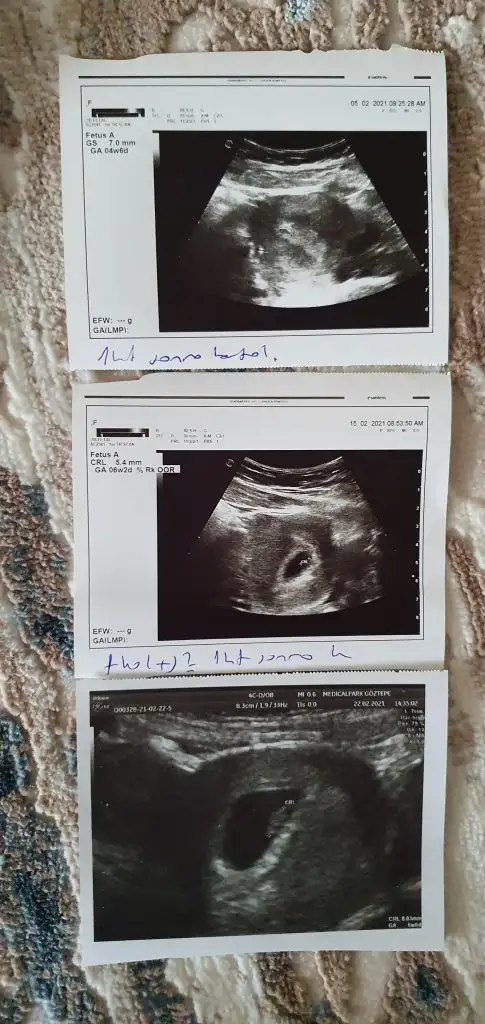

Hayırlı olsunMerhabalar kızlar dün çift çizgi testten sonra 1209beta ile gebe olduğumu öğrendim. Vajinal ultrasonda bakalım dedi ben istemedim istemiyosan bakmayalım ozaman pazartesi gebe kliniğine gel dedii.Çok korkuyorum dış gebelik olursa kese görünmezse kalp atışı olmazsa diye. Pazartesi tam 5.hafta sizce kese karından görülür müü? Sata göre 4+3 benide listeye ekler misiniz. @Kedilervekitaplar

Aa nasıl yaa :))Kızlar ramzi teorisi tutuyor kime baktım sa doğru çıktı oğluma da baktım tuttu. 6. 7 haftalık ultrason resimleri varsa bakalım cinsiyete

İki günde bir vermeye gerek görmedi canım. Pazartesi gidicem inşallah sağlıklıdırHayırlı olsun2 günde bir kan verip değeri takip edin inşallah olmaz dış gebelik. Benim karından 5+1 de görünmedi 5+4 te tekrar gittim ozaman göründü ama vajinal de baktırabilirsin bir sorun olmaz

bakabilirseniz sevinirim ama aklima takilan foto cektigimizde sag sol değişiyor mu acaba..Kızlar ramzi teorisi tutuyor kime baktım sa doğru çıktı oğluma da baktım tuttu. 6. 7 haftalık ultrason resimleri varsa bakalım cinsiyete